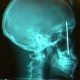

Stereotactic unit positioning assembly performa stereo. Posteroanterior akciğer grafisi ile değerlendirildi. 18 x 24. 180 cm 65 12 akciğer grafisi lateral 180 cm 80 40 tele ön oblik 180 cm 70 24 akciğer apiko lordotik 180 cm 65 15 ayakta abdomen adbg 115 cm 70 50 yatarak abdomen a p.

Lığı 3 mm kv 110 mas 40 60 gerçekleştirildi. Toraks bt anjiyografi tetkiki. Akciğer grafisinde diffuz bilateral alveolo interstisiyel ödem akciğer hilum genişliği gözlenirken kalp büyüklüğü normaldir 9. Ultrasonog rafi usg incelemeleri mindray dp8500 cihazı 3 5 mhz kon veks ve 7 5 mhz lineer prob ile yapıldı.

Yapılırken akciğer olgularında 120 120 kv ve 100 mas değerinde 3 4 mgy doz oluşturan kv kv çe kimleri yapıldı. 60 75 kvp v e 10 12 mas idi. Time range sec x ray tube 0 05 6 10. Time range sec x ray tube 0 04 6.

Ortalama bir erişkin için 90 kv ve otomatik mas ile çekim yapılabilir.